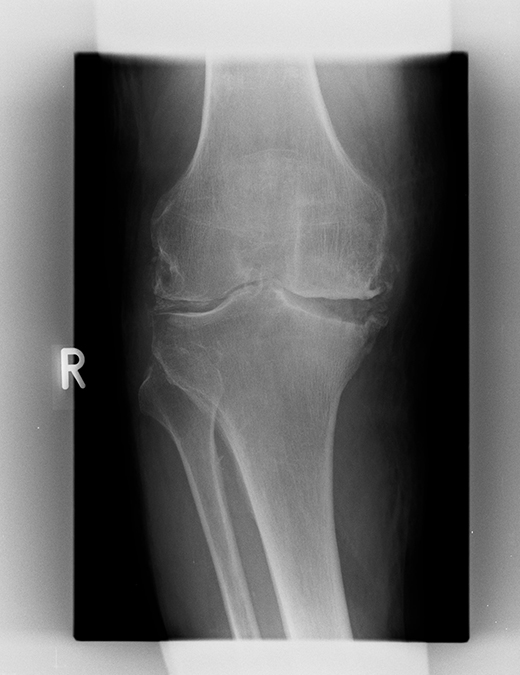

Fortgeschrittene O-Bein-Arthrose rechts mit knöchernem Defekt im innenseitigen Schienbeinbereich und 20° Streckdefizit.